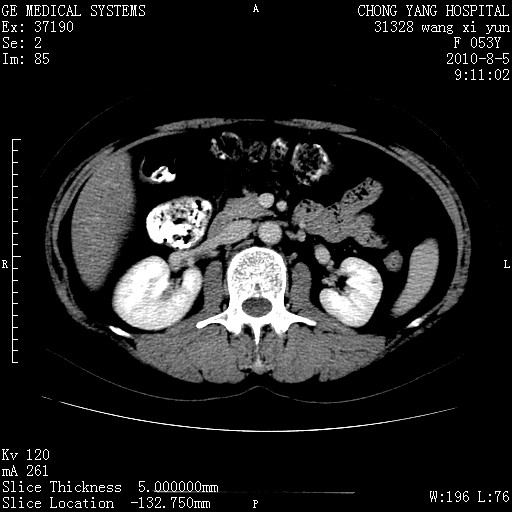

标题: CT28214:F41Y 血尿二十天,建议盆腔平扫加增强。

胆管细胞ca?

1)考虑肝左叶胆管细胞癌。2)脂肪肝。

支持胆管细胞ca。